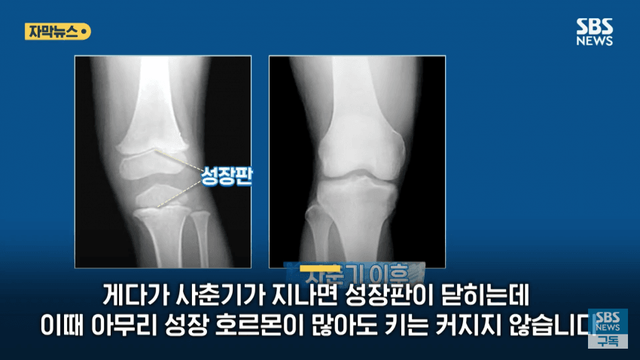

이것도 아님 성장 호르몬 맞는다고

유전자로 정해진 키를 초과해서 180넘게 자라 게 한다는류의 논문도 없고 결과도 없음

뉴스글을 보면 요즘 학생들은 20살 이전에 본인 max키를  찍는경우가 많음

남,녀 불문 그래서 키큰 학생들이 많은거고